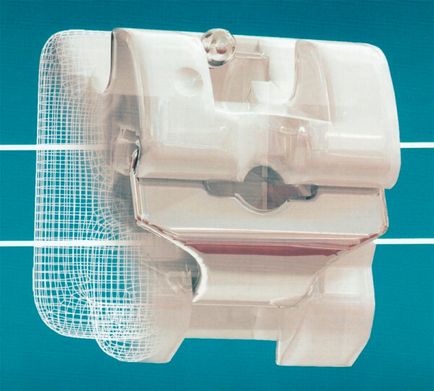

Önligírozó rögzítő rendszer - elemi egysége kapcsok vannak rögzítve a fogak, és egymáshoz rögzíthető fém ív.

Ezzel szemben, a megvalósítási módok bezligaturnyh hogy tartsa a helyén és rögzítése az ív, a zár egy reteszt vagy rugalmas klip.

Ebben az esetben, bár az ív van rögzítve a barázdák a rögzítő rendszer, akkor nem rögzült, és szabadon mozognak őket.

- Megvalósítása a legkisebb kényelmetlenséget a betegnek. Mivel a önligírozó építési mentes kiálló horgok, ötvözetek és sima élek, ezek kevésbé okoz kényelmetlenséget, mint más rendszerek.

Ezen kívül, a legtöbb esetben, ezek valamivel több terjedelmes, mint a hagyományos (vastagság, átlagosan több mint 1 mm), és hogy megszokták őket, és hogy ne észre a beteg igényel valamivel több időt.

Fém zárójelek bezligaturnogo típusú jellemzi nagy szilárdságát és rugalmasságát. Ezeket fel lehet használni, beleértve allergiások, hiszen vannak lehetőségek, amelyek öntve hipoallergén ötvözetek.